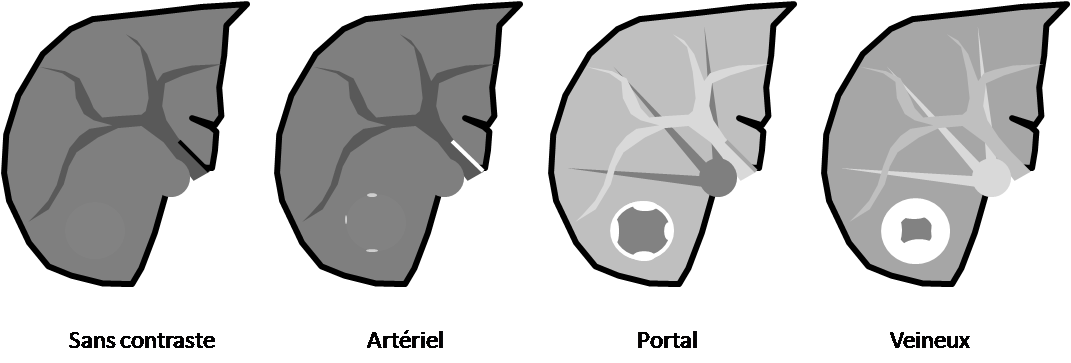

Critères sémiologiques d’hyperplasie nodulaire focale